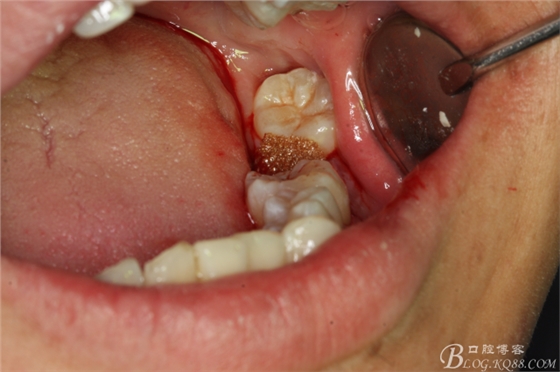

圖16.挺出47牙根

圖17.持針器牽引出47牙根

圖18.牙根取出后,牙槽窩形狀未改變

圖19.牙槽窩放膠質(zhì)銀止血海綿